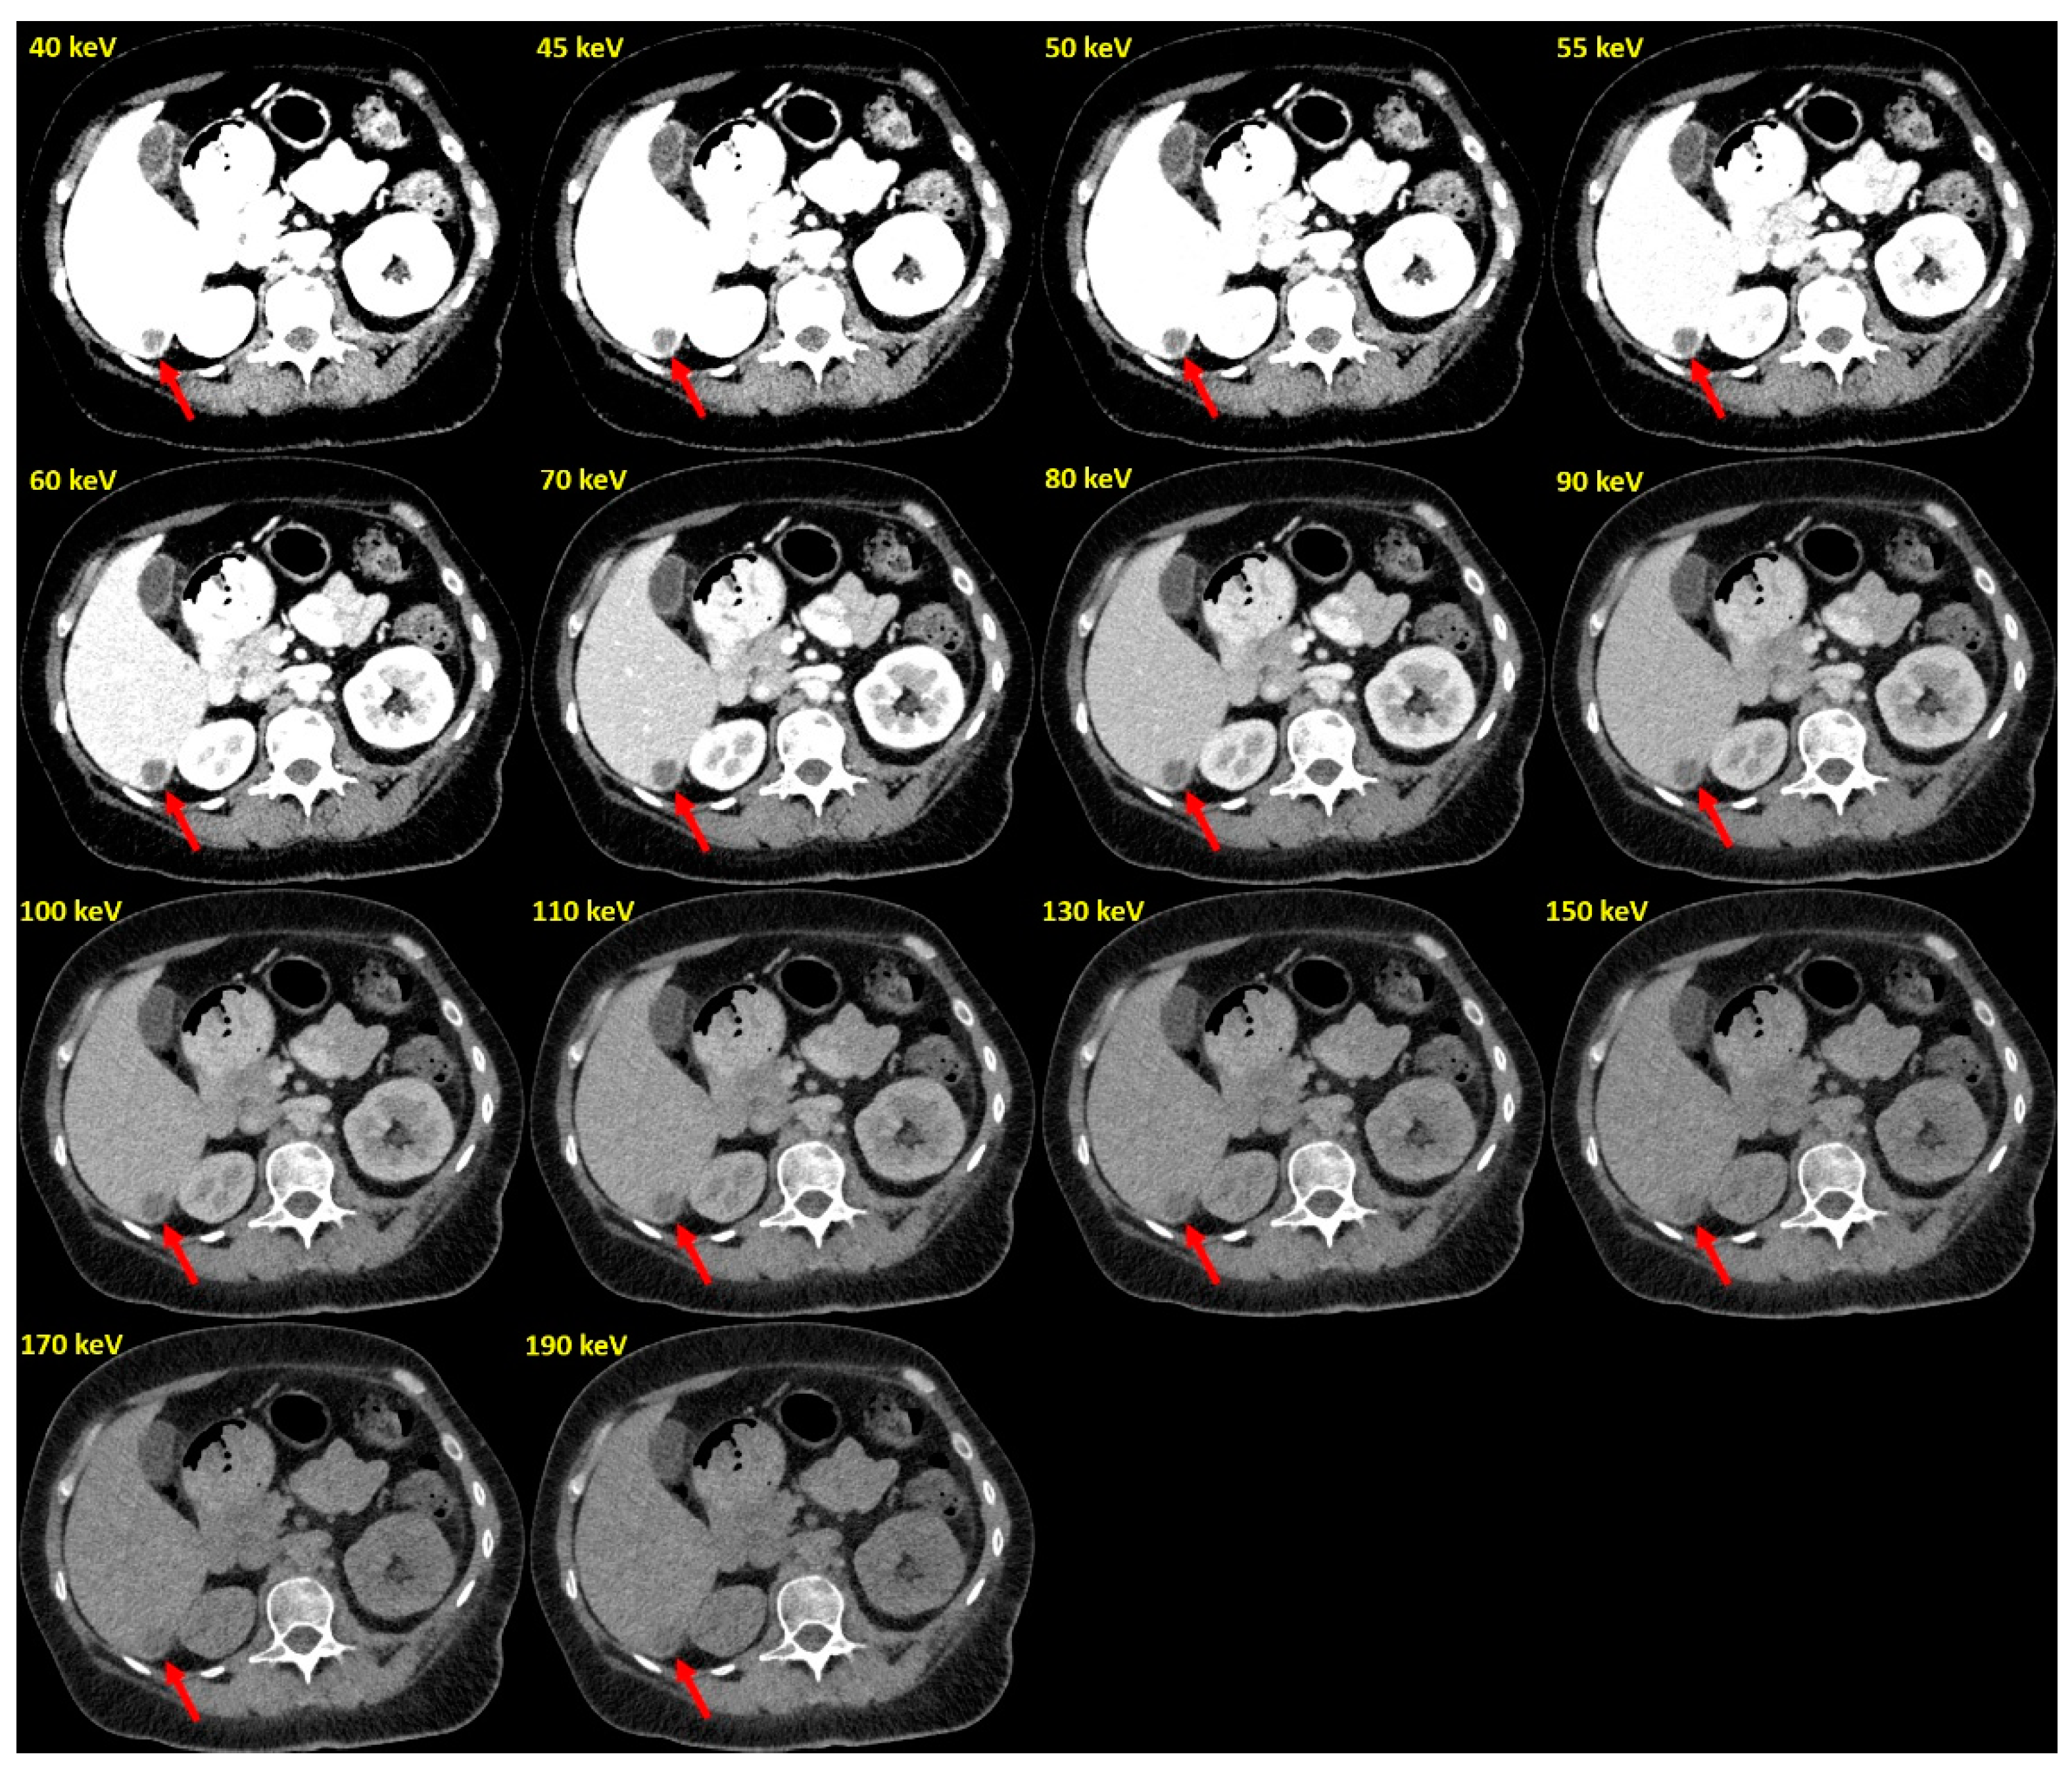

Figure 4.

Example of PCD-VMIs (40–190 keV) in a patient with hypovascularized liver metastases of pleura mesothelioma. Hypovascularized metastasis in segment VI (arrow).

In the PCD-CT group, contrast-to-noise ratio (CNR) had its maximum at the low end of the keV spectrum (6.88 [4.79; 10.19]) and continuously decreased with increasing keV levels, reaching 1.78 [1.02; 2.22] at 190 keV (Figure 3, Table 2). Significantly higher CNRs were observed for VMIs ≤ 70 keV (5.57 [4.12; 7.79]) compared to VMIs > 70 keV (2.44 [1.78; 3.34], p < 0.001).

Reconstructions at 70 keV VMI (PCD-CT) showed similar CNR to the EID-CT-series (4.41 [3.64; 6.45] vs. 4.31 [3.11; 5.17] p = 0.054). At lower keV levels (<70 keV), CNRs of PCD-CT datasets exceeded those of EID-CT datasets (Figure 3 and Figure 4 and Table 2).

In the PCD-CT group, TLR was lowest (and thus conspicuity highest) at the low keV end of the VMI spectrum (40 keV: 0.37 [0.27; 0.53], Figure 3, Table 2). With increasing keV levels, TLR increased steadily, reaching 0.58 [0.47; 0.69] at 190 keV VMI reconstructions. TLRs for VMIs ≤ 70 keV (0.38 [0.29; 0.54]) were significantly lower than for VMIs > 70 keV (0.53 [0.41; 0.63], p < 0.001). Reconstructions at 70 keV VMI (PCD-CT) had similar TLRs to those of EID-CT datasets (0.41 [0.33; 0.52] vs. 0.41 [0.32; 0.51], p = 0.756, Table 2), while lower keV VMI reconstructions showed significantly lower TLRs and thus higher lesion conspicuity (Figure 3, Table 2).